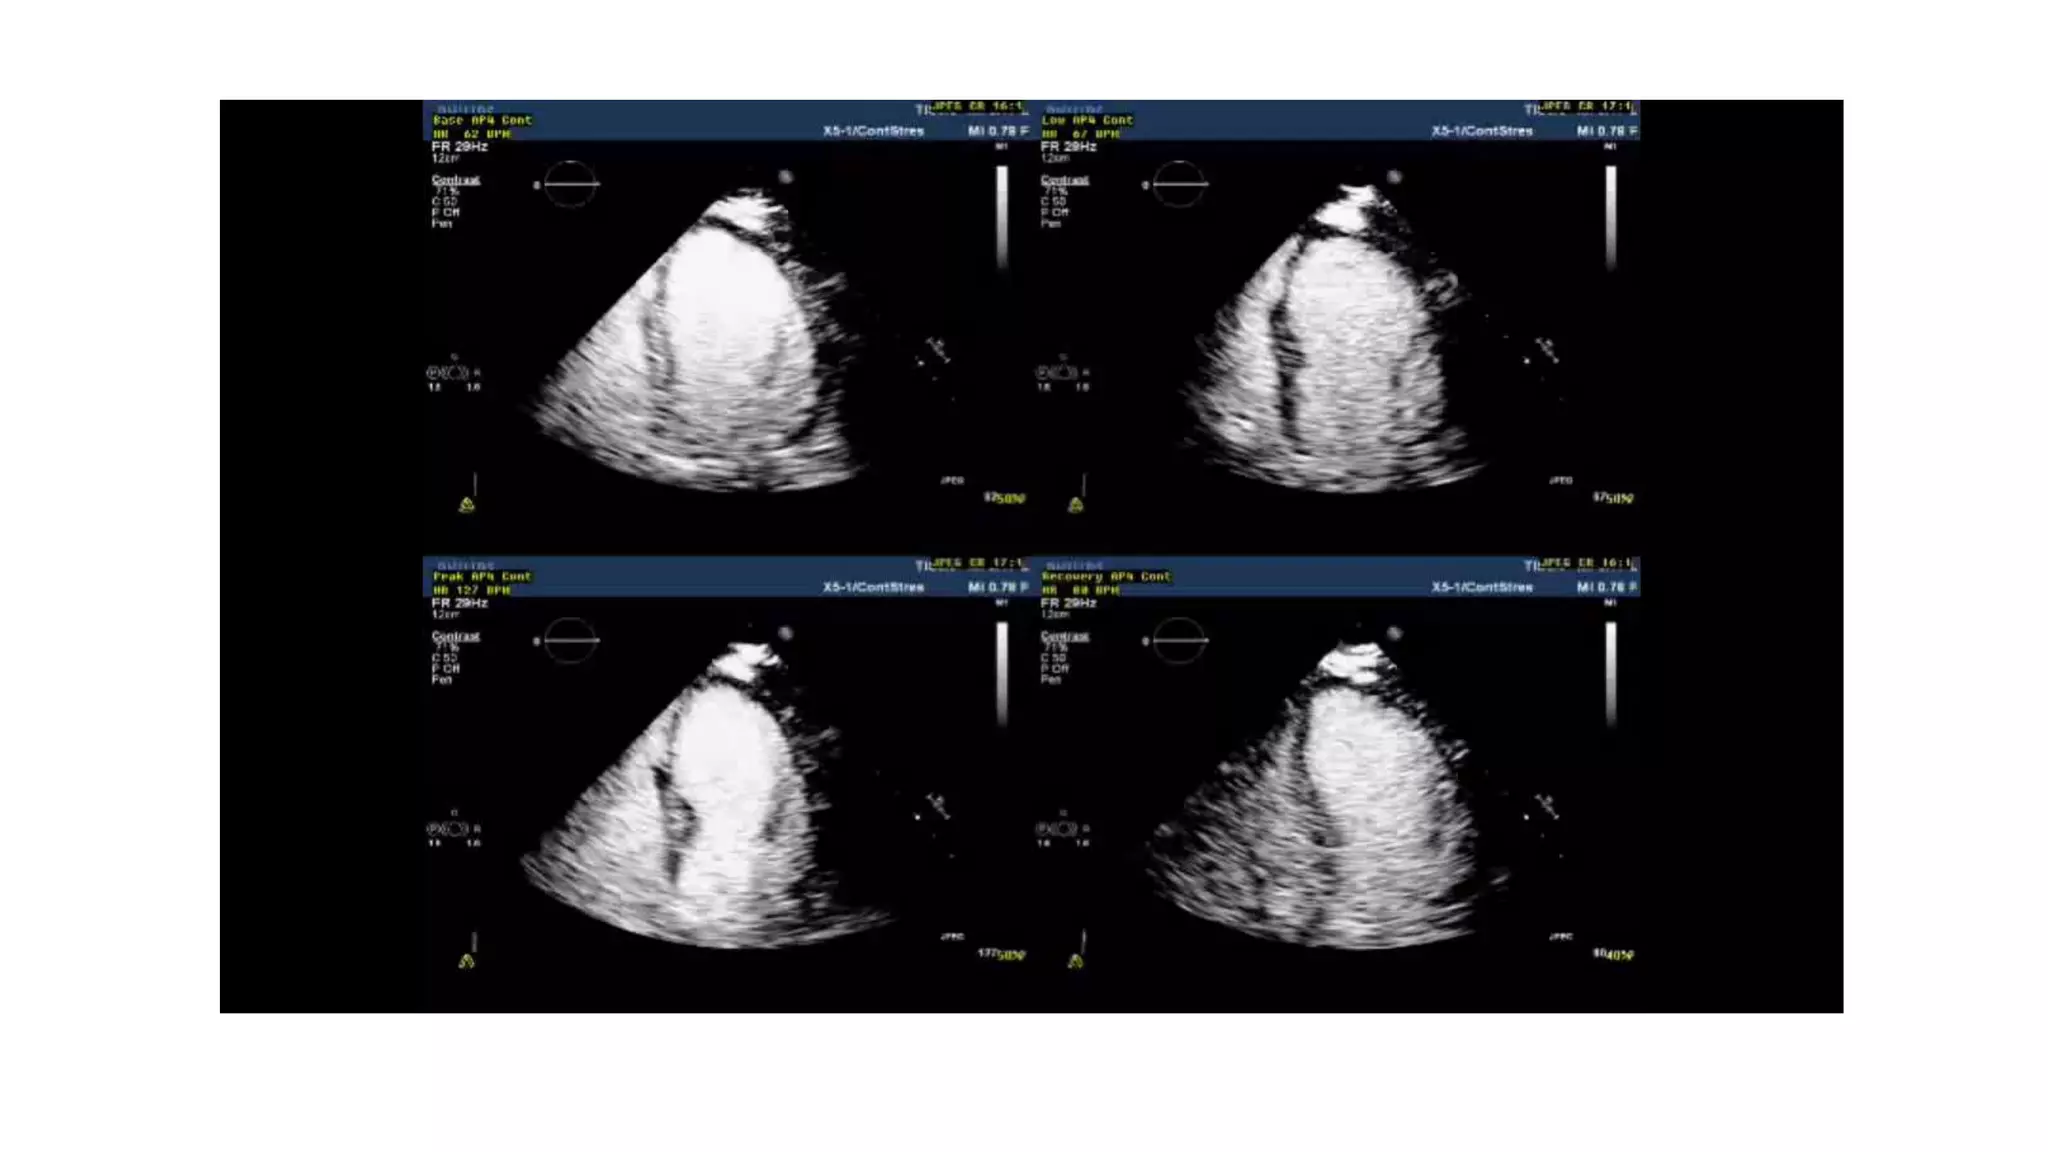

• The protocol was defined by ASE(2007) & ESE(2008)

• Machine should have the ability to trigger image acquisition based on ECG

• Also machine should have split screen & quadruple screen so that simultaneous comparison

of image is possible

• Contrast enhancement should be considered to augment endocardial definition when ≥ 2

contiguous endocardial segments not visualized at rest.

• Images at each echocardiographic window are obtained during rest, low-dose, intermediate

dose, peak-dose & post-stress